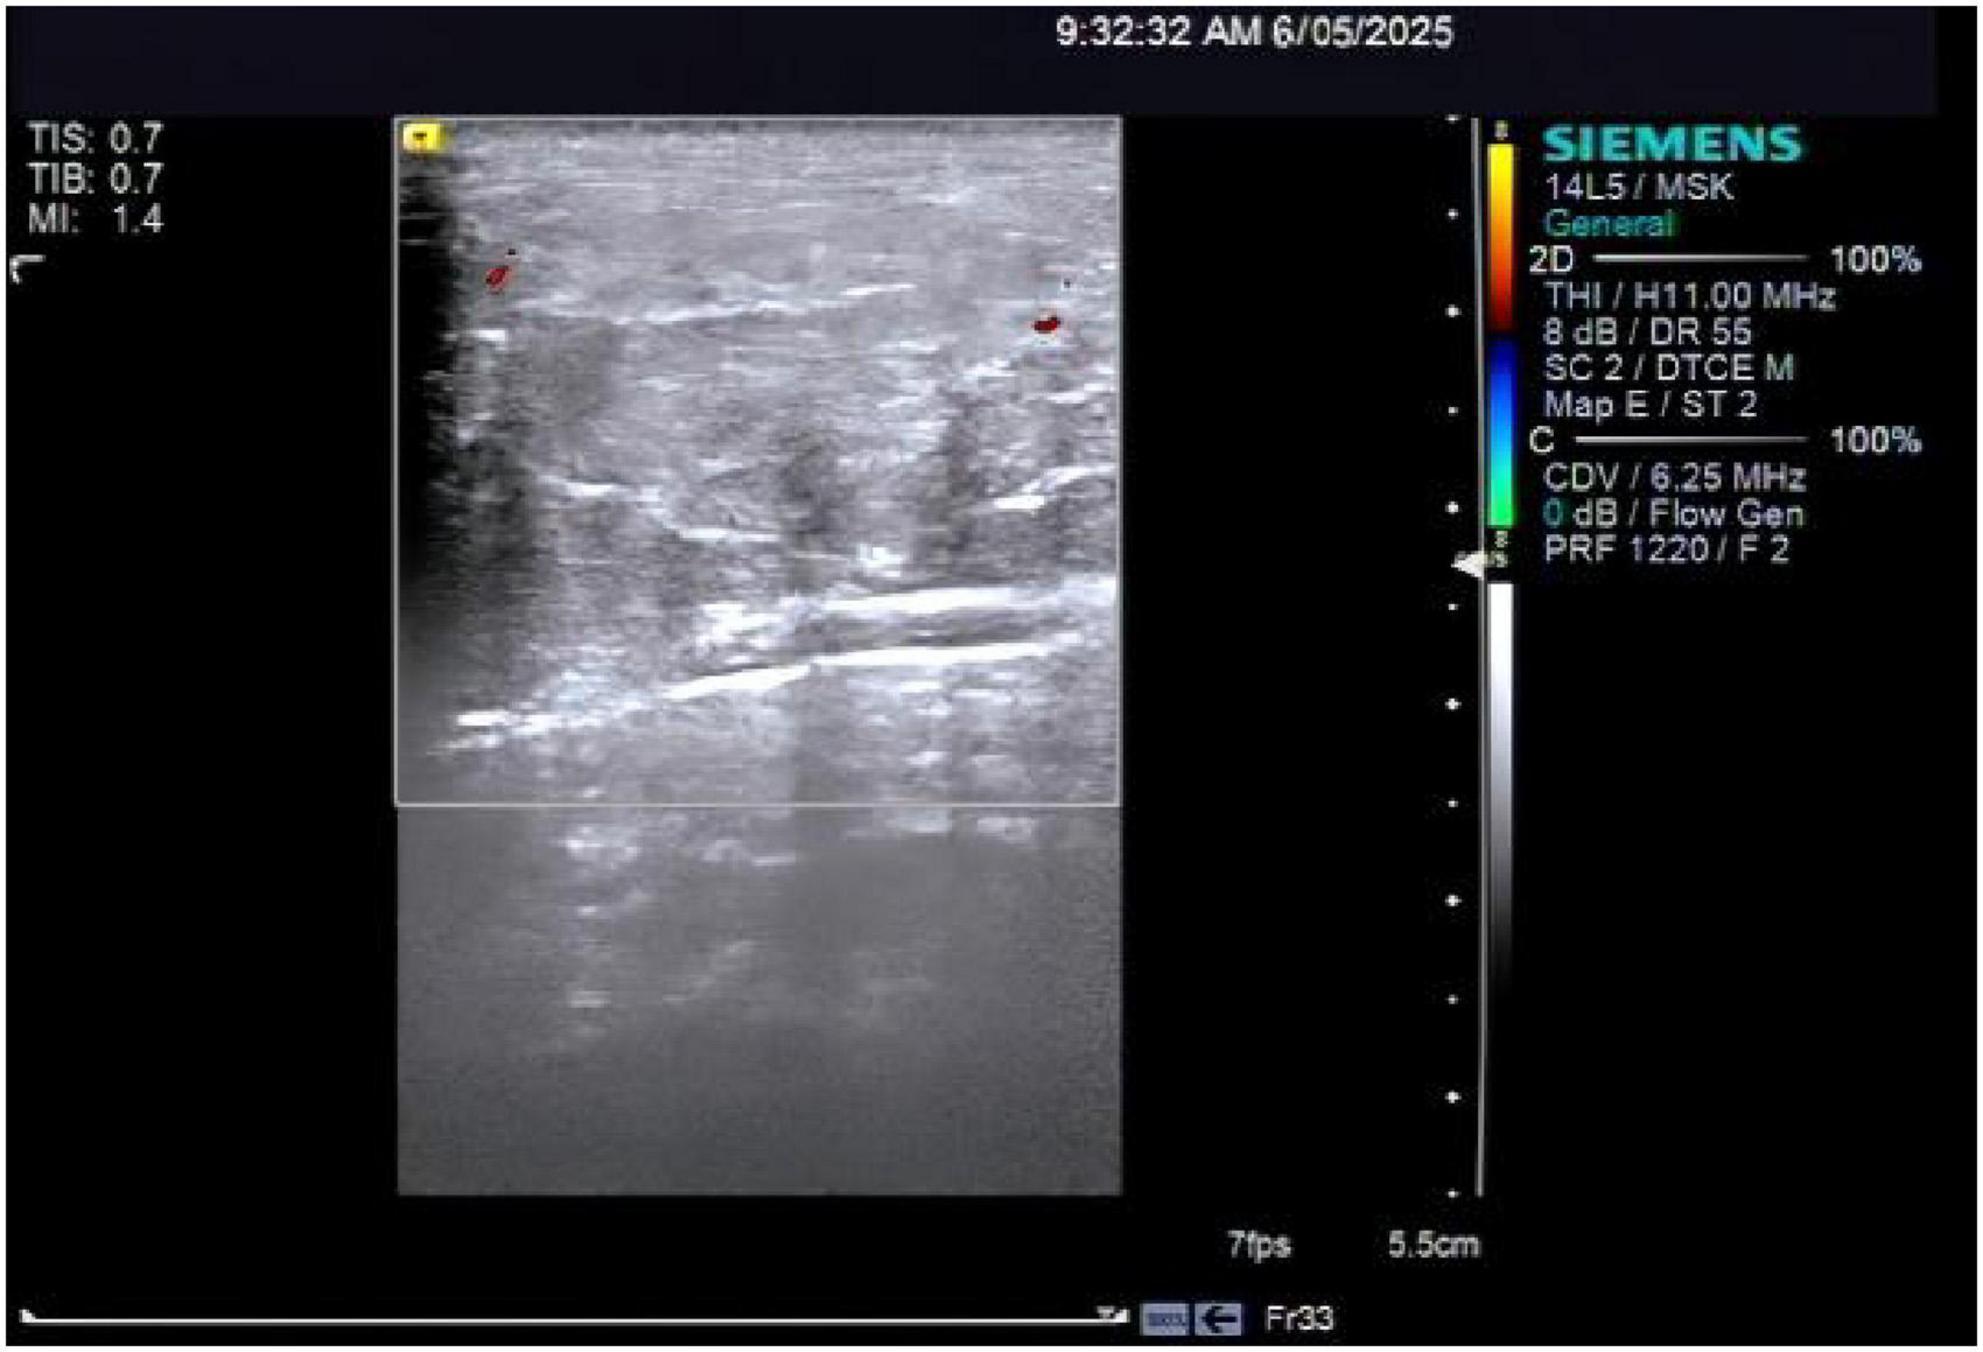

Background Madelung's disease (MD) is a rare disorder of fat metabolism, with symptoms often characterized by the appearance of chronic accumulations of abnormal adipose tissue in areas such as the neck and neckline, upper back and chest. Nowadays, its pathogenesis is still unknown, and some scholars have suggested that its etiology is closely related to alcohol consumption, and that it is associated with a variety of metabolic diseases such as liver disease, hypertension, diabetes mellitus, dyslipidemia, and peripheral neurological damage. Currently, there are very few reported cases of Madelung's disease complicated by alcoholic liver disease and liver cirrhosis (LC), making this case worthy of reporting. Case summaries This article reports on a 60-year-old man, the main point of view"The patient has experienced edema in both lower limbs for two weeks , accompanied by a long history of alcohol consumption".Clinical examination showed subcutaneous swelling of the neck, which has been clearly present for three years. The diagnosis of Madelung's disease combined with alcoholic liver disease and liver cirrhosis was made based on laboratory tests of liver function, ultrasound of the neck vessels, ultrasound of the superficial tissues of the neck, and CT of the abdomen. The patient has not exhibited restricted neck mobility or symptoms of tracheoesophageal fat syndrome, which affects swallowing and breathing, and refused neck surgery treatment and received hepatoprotective therapy and traditional agents. After 14 days and two cycles of Chinese medicine,edema subsided, and the size of the subcutaneous mass remained stable. Result Madelung's disease is often underdiagnosed and misdiagnosed because of its low prevalence. The purpose of this article is to illustrate the need to be vigilant in clinical encounters with patients with Madelung's disease combined with alcoholic liver disease and liver cirrhosis, to achieve early intervention and treatment, and to prevent complications. The etiology of this disease remains unclear. Further research into its pathophysiological mechanisms should be pursued, opening new avenues for therapeutic investigations.